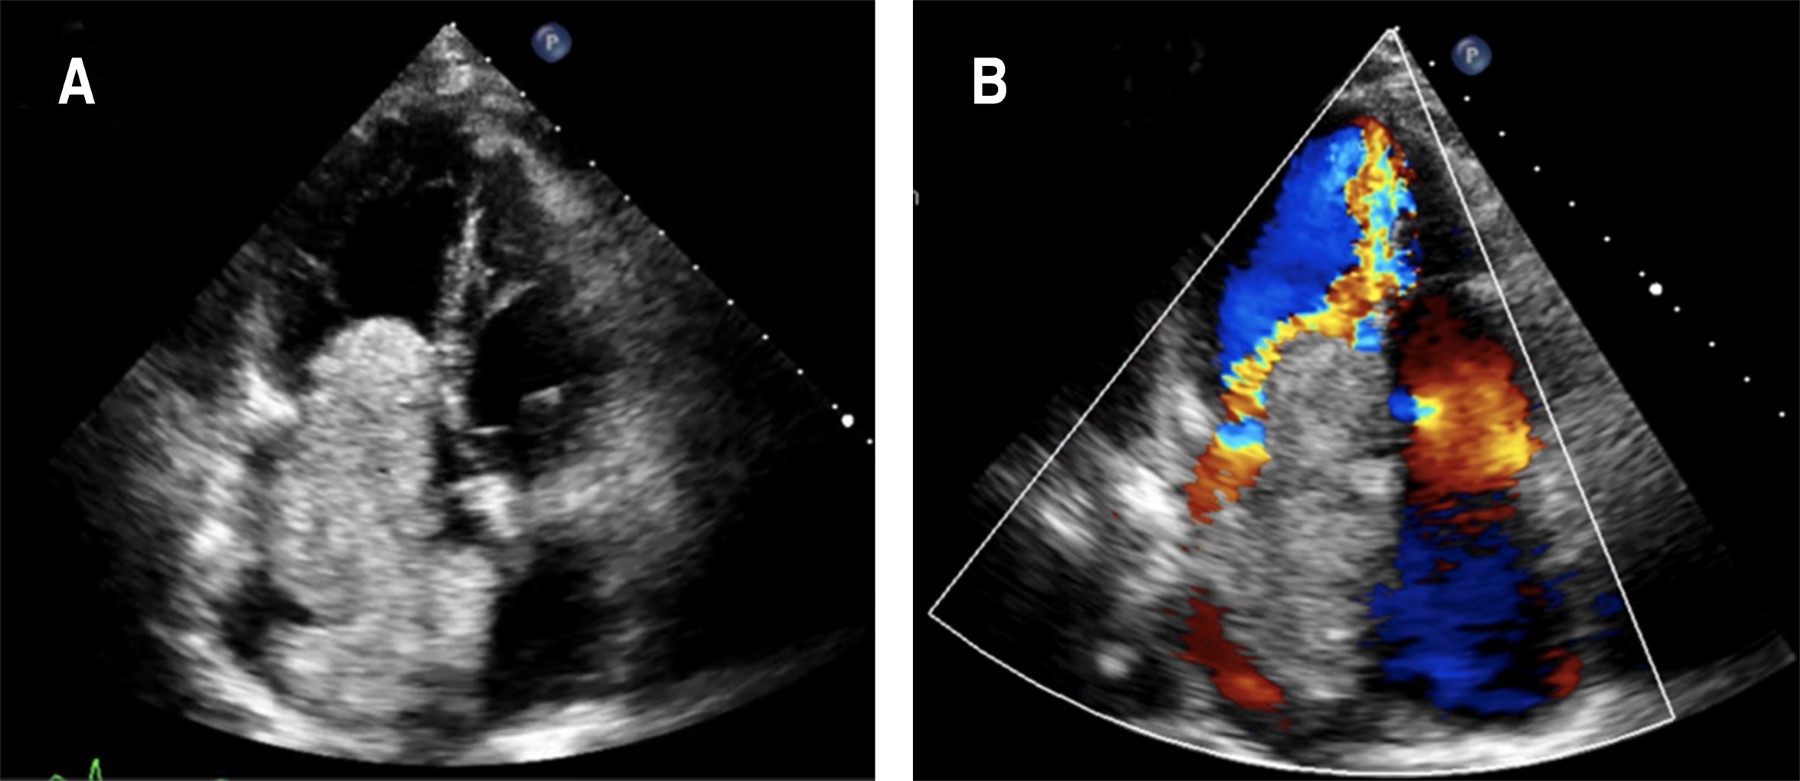

Introducción: los mixomas son los tumores cardiacos primarios más comunes, en 75-85% se localizan en la aurícula izquierda y suelen tener predominio por el sexo femenino. Se pueden presentar con la triada de obstrucción cardiaca, embolismo o síntomas constitucionales. Presentación del caso: en este trabajo se presenta el caso de una paciente joven, quien dos años antes del diagnóstico comenzó con disnea de medianos esfuerzos, la cual cedió con el uso de un betabloqueador, posterior a una intervención quirúrgica comienza con datos de falla cardiaca, se le realiza un ecocardiograma donde se evidencia una masa que abarca la mayor parte de la aurícula izquierda y protruye a través de la válvula mitral hacia el ventrículo izquierdo. Conclusión: el ecocardiograma transtorácico es la primera línea de imagen para el diagnóstico del mixoma, sin embargo, la resonancia magnética provee información sobre la localización, tamaño y caracterización de la masa, además de ayudar al diagnóstico diferencial con presencia de trombo, datos indispensables para el abordaje y tratamiento del paciente.

Figura 1